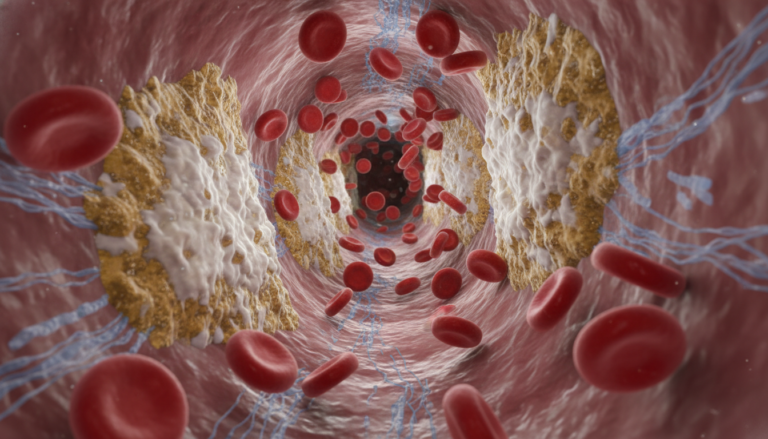

4. Damages Arteries

High blood pressure harms the inner lining of arteries, making them more prone to plaque buildup (atherosclerosis). This reduces blood flow to the heart.

5. Increases Risk of Heart Attack

Blocked arteries can cut off oxygen supply to heart muscles, leading to a heart attack. Hypertension is one of the top risk factors for cardiovascular disease.